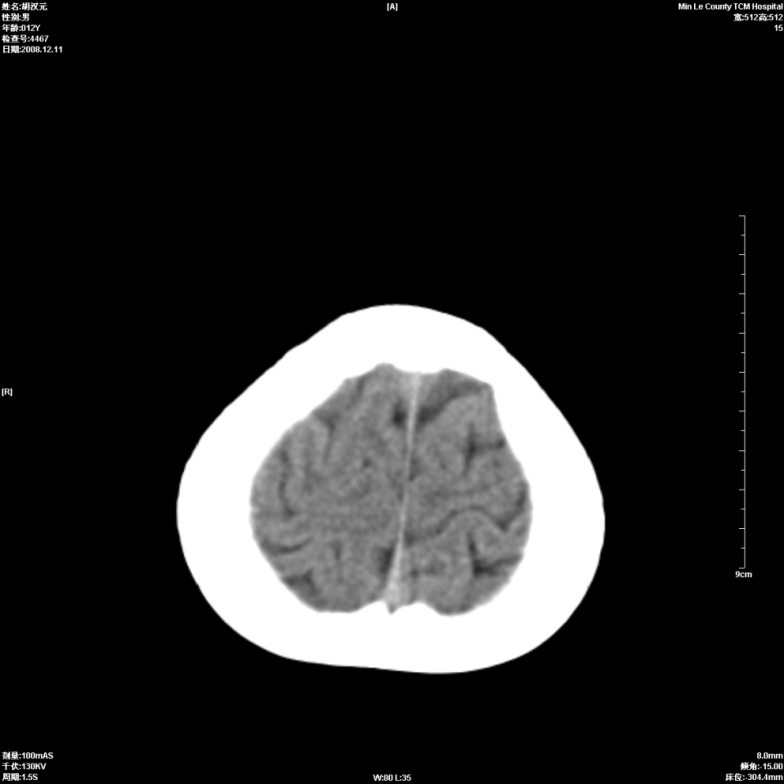

标题: PED1681:头疼发热约一周 [打印本页]

标题: PED1681:头疼发热约一周

两侧顶部近灰质处白质密度降低,是否炎性改变

颅脑ct轴位平扫颅内未见明确异常;建议必要时复查或行进一步检查。

两侧顶部近灰质处白质密度降低,建议mri